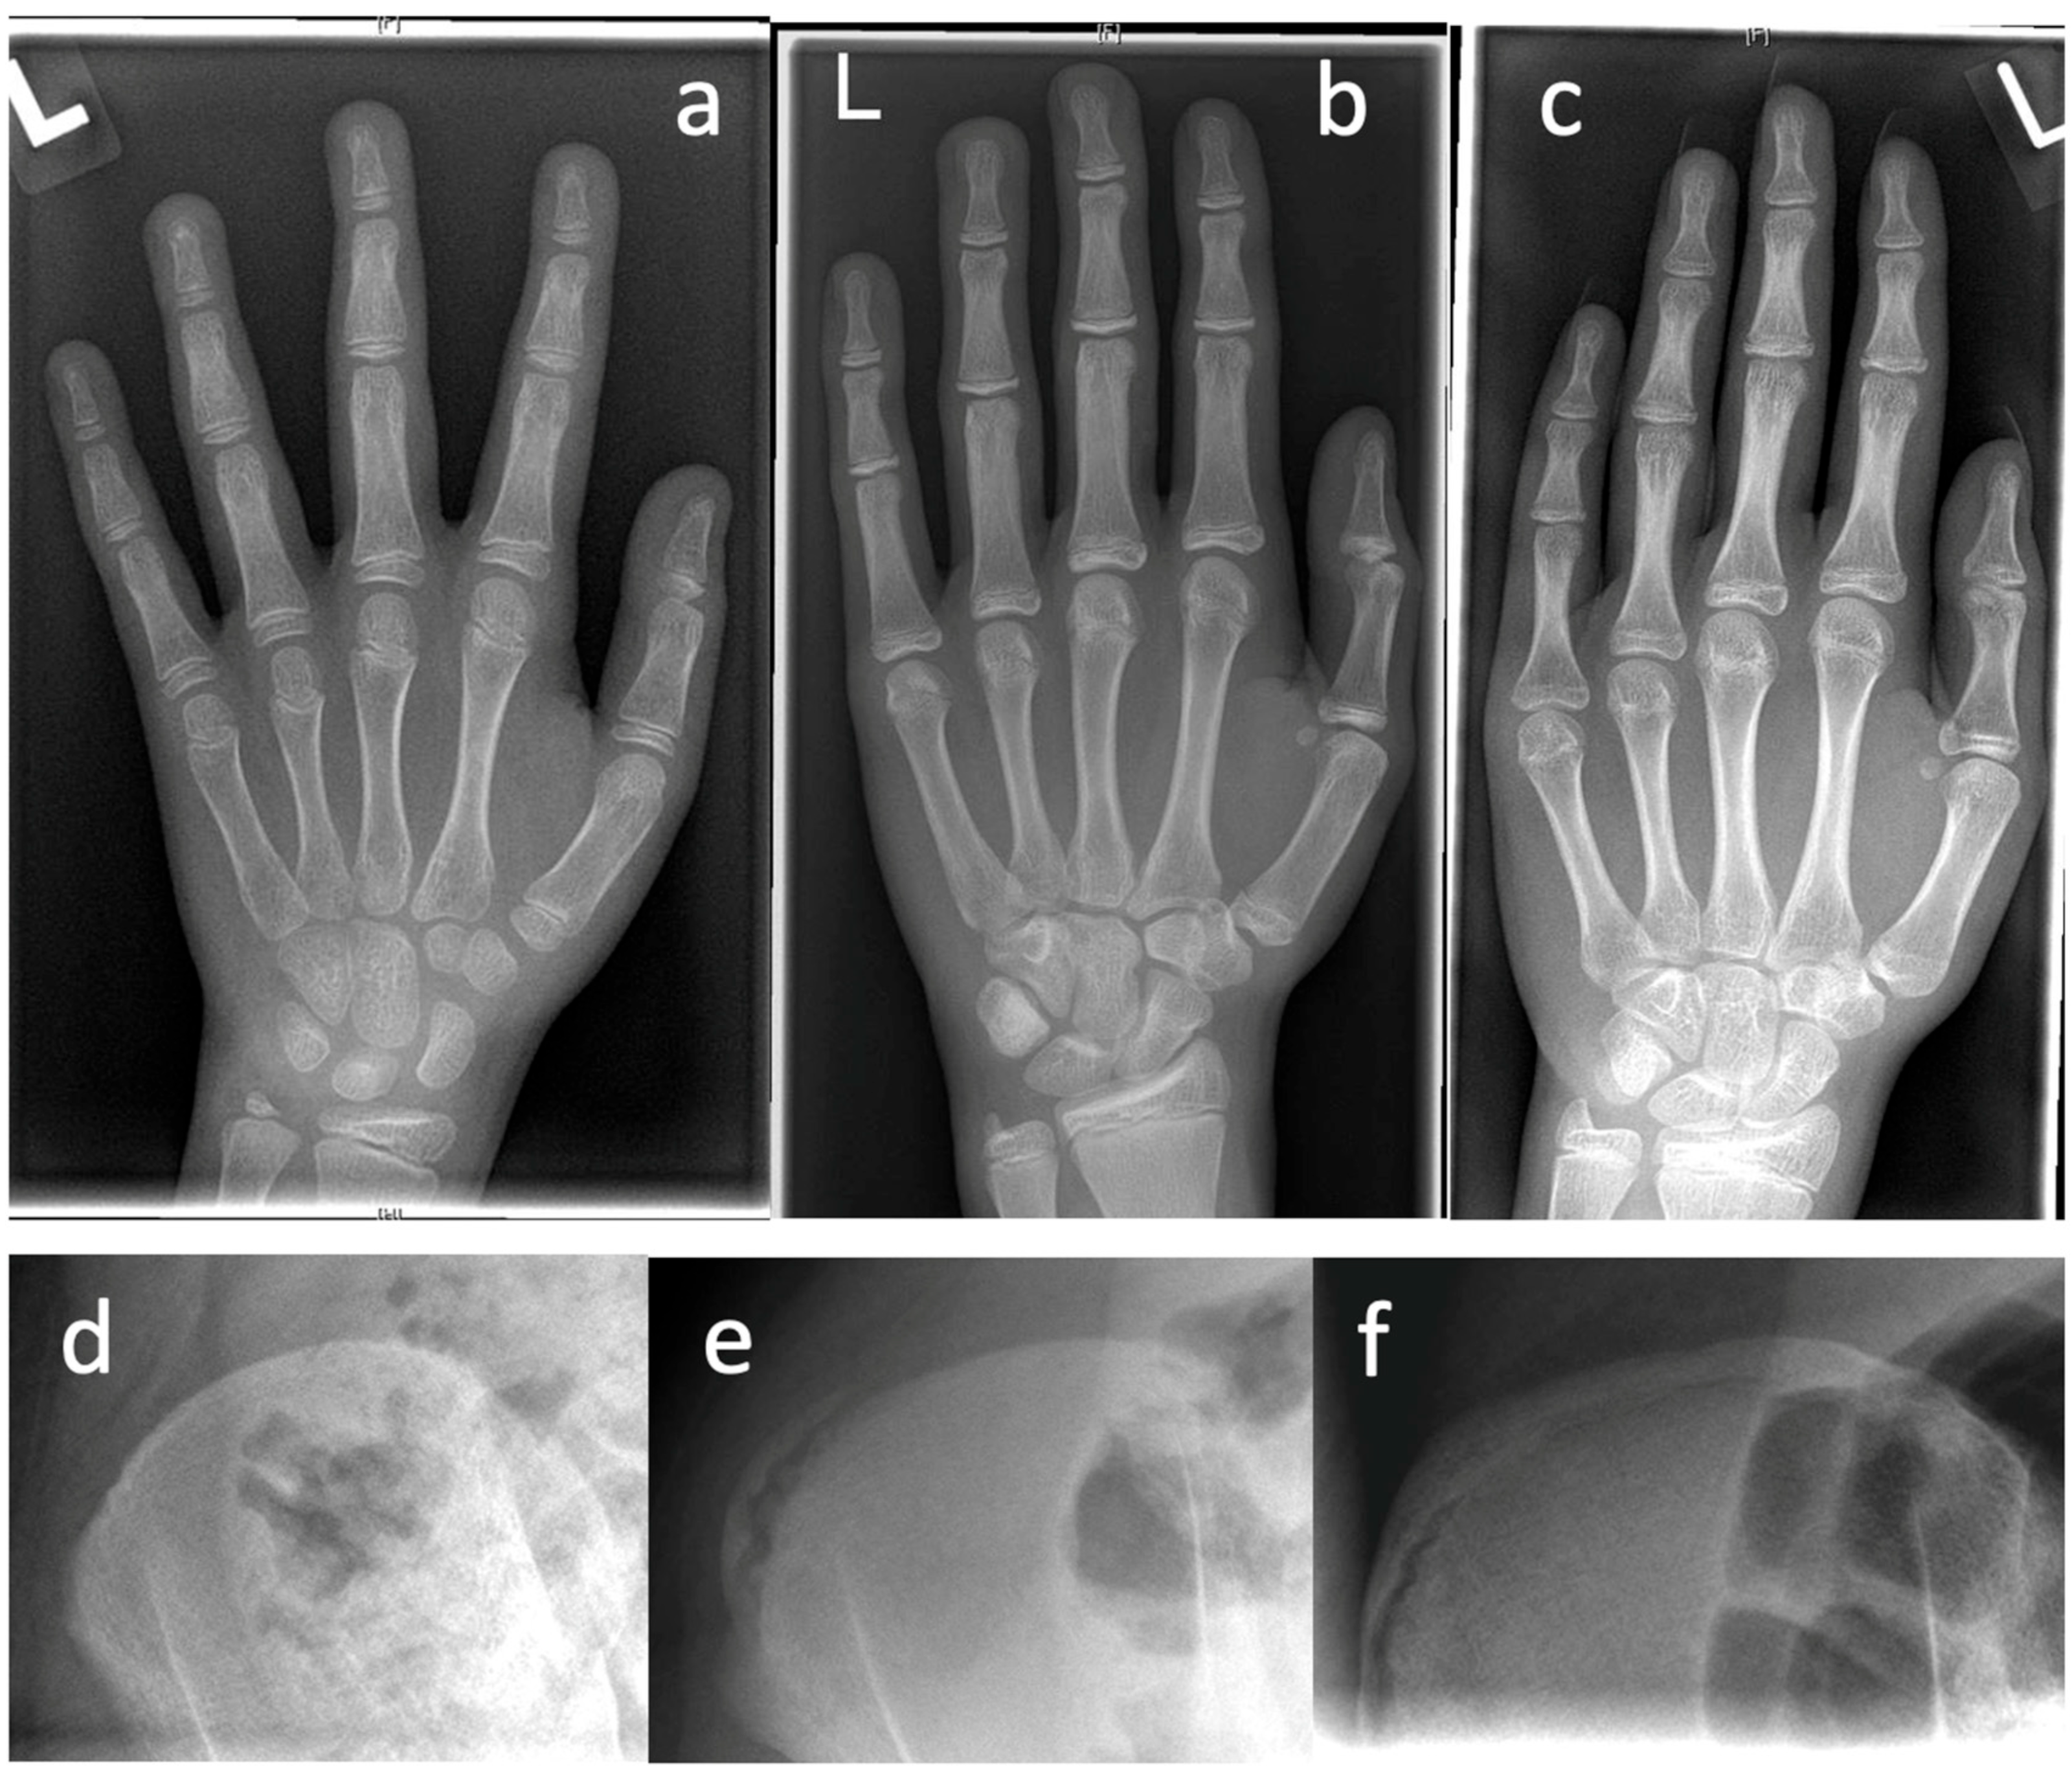

Figure 1. Examples for determination of growth potential according to Sanders of ne non-dominant left (L) hand [21]. (ac) and Risser [22] (df), (a)—Sanders 2, (b)—Sanders 3, (c)—Sanders 5, (d)—Risser 0, (e)—Risser 2, (f)—Risser IV.

3.4.3. Growth Prognosis

Before initiating surgical therapy, knowledge of the patient’s growth potential is of immense importance, since without possible residual growth, some of the procedures cannot guarantee sufficient improvement of the extent of scoliosis. Spinal growth can be estimated on clinical and radiographic parameters. First, in girls, the onset of menarche is considered the point at which the pubertal growth spurt is complete and the growth tendency has already diminished. In most cases, the spine is fully grown about 2 years after the onset of menarche. In boys, the comparable counterpart is the change of voice. The most widespread radiographic method of determining the growth tendency and thus the ability of the spine to be corrected is based on the degree of ossification of the iliac apophysis according to Risser [22]. The iliac apophysis is divided into 6 stages according to different stages of ossification of the apophysis, which begins at the lateral iliac crest and progresses medially. A more reliable measurement is the Sanders classification (simplified Tanner–Whitehouse III system) using an X-ray of the non-dominant hand [21]. The state of ossification of the epiphyses of the hand and wrist defines the expected skeletal growth in 8 groups: juvenile slow (1), preadolescent slow (2), adolescent rapid (early) (3), adolescent rapid (late) (4), adolescent steady (early) (5), adolescent steady (late) (6), early mature (7), mature (8).